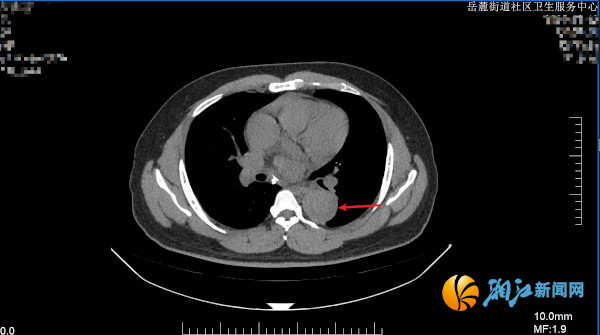

图说:胸部CT平扫纵隔窗提示胸主动脉增宽,管腔内弧形低密度影。

入院后监测显示,赵先生血压高达180/120mmHg(右侧)、180/116mmHg(左侧)。尽管患者并无明显胸闷、胸痛等典型症状,医护人员仍迅速完善胸部CT等相关检查。放射科主任张诗颖通过影像学表现进行专业判读,提示高度疑似主动脉夹层,相关结果立即引起医护团队的高度警觉。